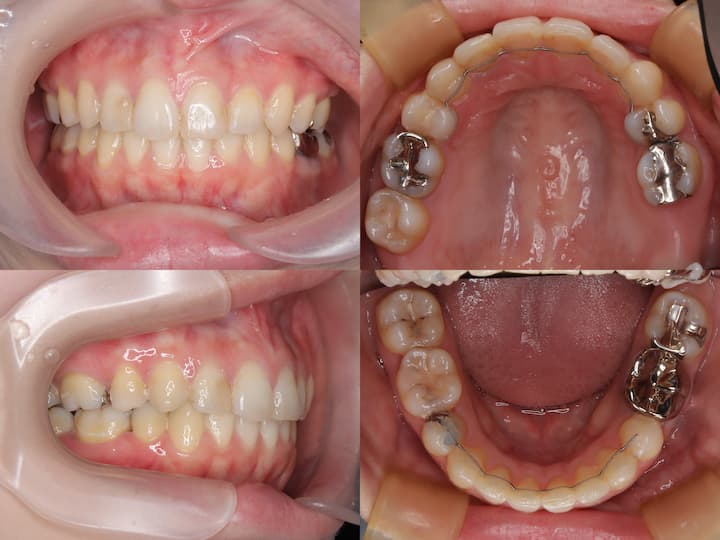

開咬(オープンバイト)のマウスピース矯正治療

Before

After

治療期間: 1年6ヶ月

前歯が噛み合っていないため、上顎臼歯を圧下(上方向に移動)し、上顎前歯は挺出(下方向に移動)して治療を行いました。

大臼歯の圧下と上顎前歯の挺出

上顎大臼歯の圧下(上方向に移動)と上顎前歯の挺出(縦に伸ばす)を行いました。下顎前歯は極力挺出させず、下顎骨の回転により前歯を噛み合わせるような治療計画を立てました。

開咬(オープンバイト)は後戻りにより、治療後に再び前歯が噛み合わなくなるリスクがあります。大臼歯の圧下のみや前歯の挺出のみの治療ではそれぞれの歯の移動量が大きくなり後戻りのリスクが大きくなります。 したがって大臼歯の圧下と前歯の挺出を組み合わせることでそれぞれの歯の動きをできるだけ小さくして後戻りのリスクを減らしています。このケースでは治療終了2年後に前歯が噛み合う状態を維持できています。